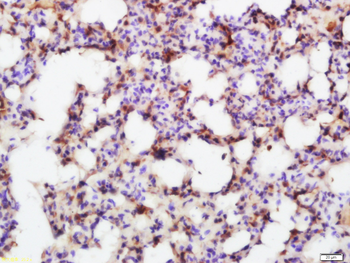

100 μl, 200 μl, 50 μlSMAD7 Rabbit Polyclonal Antibody [orb500819]

FC, ICC, IF, IHC-Fr, IHC-P, WB

Bovine, Porcine

Human, Mouse, Rat

Rabbit

Polyclonal

Unconjugated

100 μl, 200 μl, 50 μlPhospho-Smad3 (Ser213) Rabbit Polyclonal Antibody [orb106193]